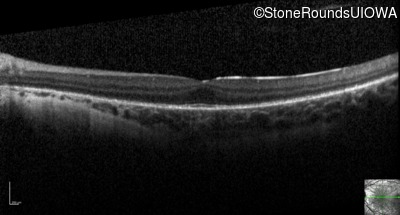

Optical Coherence Tomography - Left - 10/16 sc

Exemplar / OCT Stack